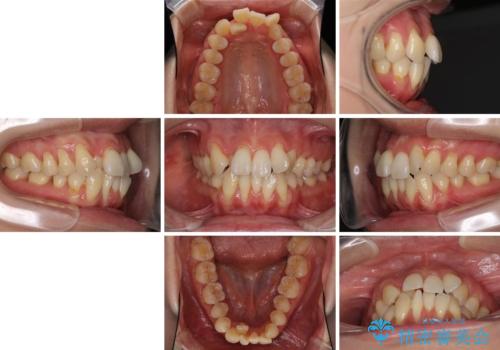

- 上下前歯のでこぼこを気にされ、矯正治療を希望された患者様です。

費用を抑えるため、メタルブラケットを採用し、抜歯矯正を行うこととしました。

通常であれば、上下顎左右小臼歯各1歯の合計4本を抜歯しますが、歯肉退縮の著しい下顎前歯を抜歯して欲しいという患者様の強い希望により、上顎のみ左右小臼歯2歯を、下顎は前歯を1歯を抜歯することとしました。

抜歯する歯を変更したため奥歯の咬合はアンバランスとなりましたが、前歯は綺麗に整い、歯肉退縮も回避できました。